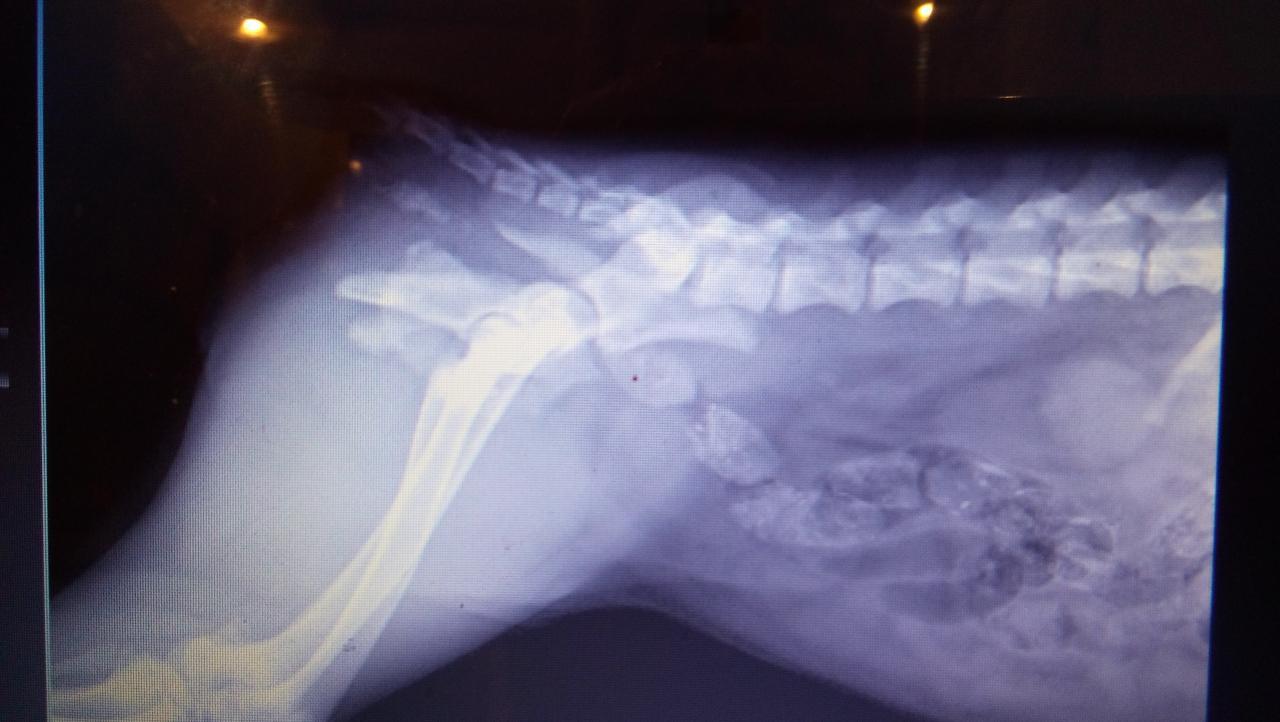

Позавчера днем собака, девочка 6 месяцев была сбита машиной ОДЕССА, ул. Невского. Перелом таза, перелом подвздошной кости. Вертлюжной впадины, седалищной кости, смещение по кресцовому сочленению, травма мочевого пузыря. Первая помощь оказана, но необходима срочная операция. огромная просьба всех неравнодушных оказать материальную помощь. На операцию предположительно надо 6000 гр. можно в клинику vita ОДЕССА , можно на карту привата - 5168757371721533. Куратор Светлана. 0969806055